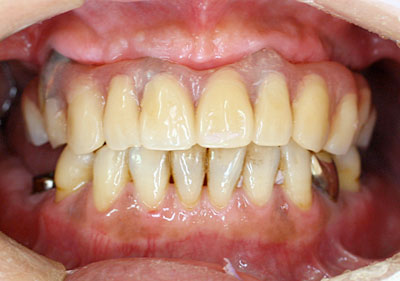

インプラントと周りの歯肉が安定したところで形をとって、最終のインプラント義歯を装着します。

ほとんど自分の歯と見分けがつかない程度にきれいになります。もちろん口蓋の部分には義歯はなく、歯だけですので違和感はほとんどありません。患者様には例外なく喜んでいただいています。このインプラント義歯は取り外しできるため、当科で1年に1度外して、きれいにします。